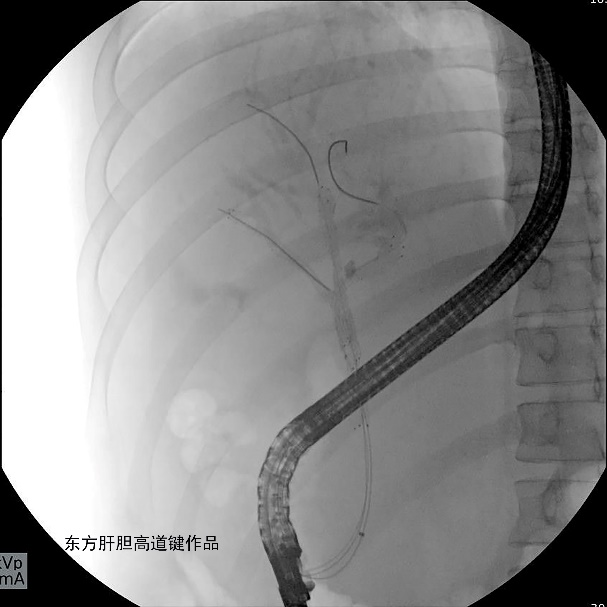

图C

图C:第三根导丝超选进入左外侧肝内胆管;